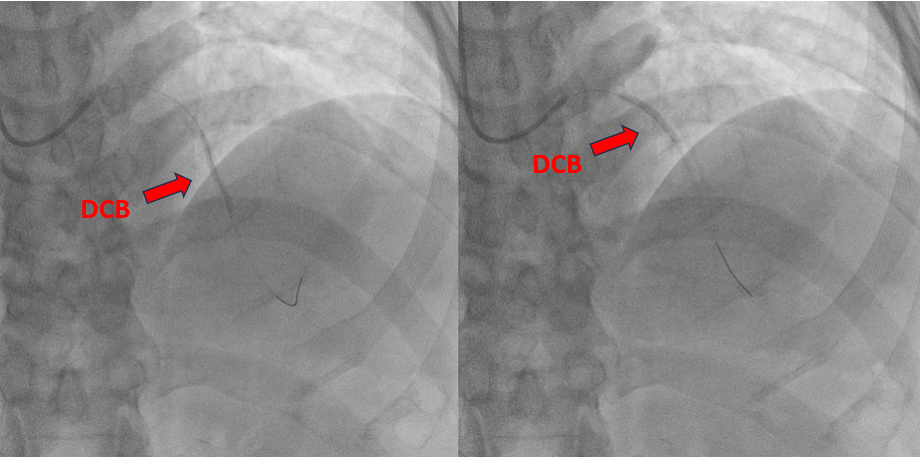

The procedure was performed via a 6 French femoral approach. The LAD was wired using a BMW guidewire and pre-dilated sequentially with non-compliant balloons sized 2.5 ¡¿ 15 mm and 3.0 ¡¿ 15 mm, achieving satisfactory lumen expansion. Considering the diffuse nature of the lesion, a DCB-only strategy was selected to avoid multiple overlapping stents. DCB angioplasty was carried out, sized 2.5 ¡¿ 30 mm and 3.0 ¡¿ 25 mm, each inflated for 60 seconds. The final angiogram revealed mild vessel recoil and a non–flow-limiting dissection with TIMI 3 flow. To optimize the result, the operator attempted re-wiring for bailout stenting; however, the guidewire inadvertently entered a false lumen. Despite this, pre-dilatation was performed followed by deployment of a 2.5 ¡¿ 26 mm Onyx drug-eluting stent from the mid to distal LAD. Subsequently, the vessel flow deteriorated to TIMI 0. Intravascular ultrasound confirmed subintimal stent placement with a long false lumen extending from the mid LAD before the septal branch. Multiple attempts to re-enter the true lumen, both proximally and distally, were unsuccessful. The patient developed chest discomfort, which was partially relieved with morphine. In view of persistent LAD occlusion, intra-aortic balloon pump (IABP) support was initiated for hemodynamic stabilization, and the patient was referred for urgent coronary artery bypass grafting (CABG).